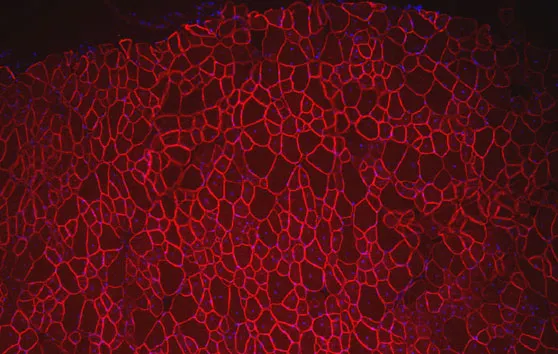

Ce traitement est un oligonucléotide antisens synthétique capable d’induire le saut de l’exon 51 du gène de la dystrophine, qui a été développé par la société Prosensa, puis par GSK, et dont les travaux initiaux ont été soutenus par l’AFM-Téléthon.